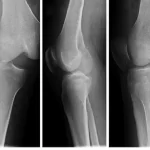

در اکثر کودکان مبتلا به قوز گردن ناشی از عادات نادرست، با تشخیص زود هنگام و برنامه درمانی اصولی غیر جراحی، بیش از ۹۰ درصد موارد بدون نیاز به عمل بهبود مییابند. اما در موارد نادر و شدید، جراحی فیوژن ستون فقرات گردنی همراه با فعالیتهایی برای تثبیت و اصلاح انحنا انجام میشود تا از آسیب دائمی به نخاع جلوگیری شده و رشد طبیعی ستون فقرات حفظ گردد. به طور کلی، تصمیم گیری نهایی همیشه باید توسط متخصص اطفال ارتوپد یا جراح ستون فقرات کودکان و بر اساس معاینه بالینی، تصاویر رادیو گرافی، MRI و ارزیابی جامع انجام شود تا بهترین نتیجه با کمترین ریسک حاصل گردد.